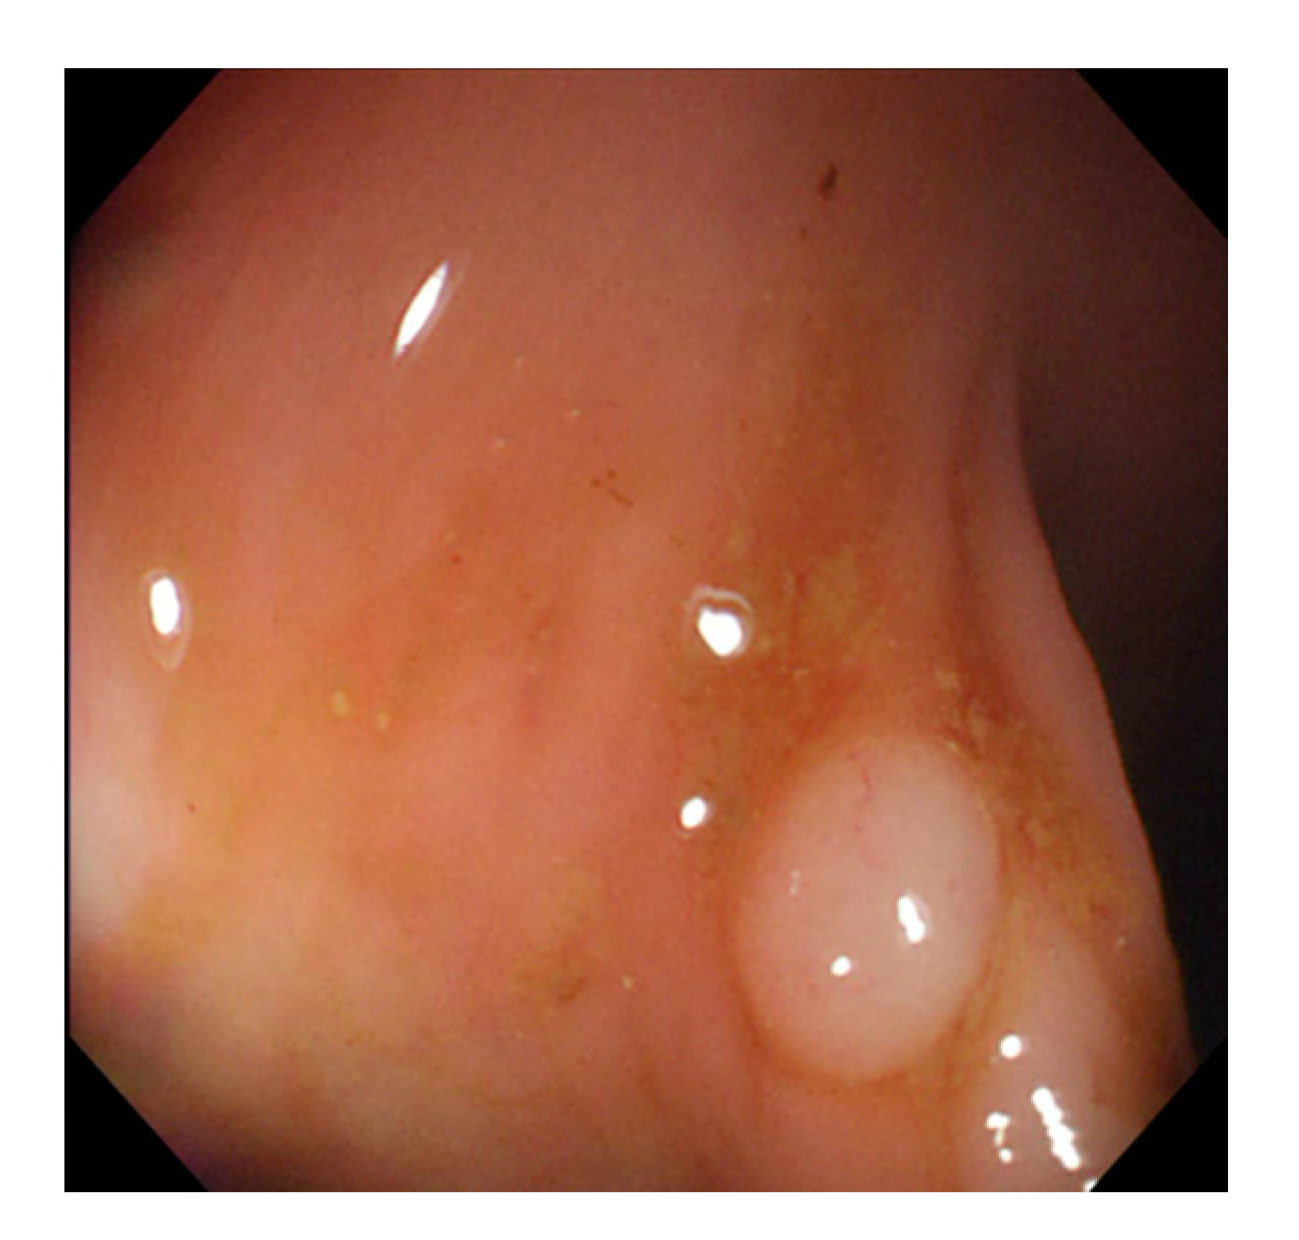

Currently, many medical images are processed into grayscale images, such as ultrasound, computed tomography (CT), and magnetic resonance (MR) images. Tan et al. [44] applied a gray-level cooccurrence matrix and CNN to CT images for polyp diagnosis. Zhang et al. [45] compress the three-channel color images of chest CT to grayscale images. A five-layer deep CNN with stochastic pooling is used to diagnose chest-based COVID-19. Xie et al. [46] mentioned that in deep learning, colors are not the key features influencing accurate image classification. They also discovered that in X-ray image classification, the speed and accuracy of processing grayscale images were considerably higher than those of processing RGB images. The grayscale method used was ITU-R Recommendation BT.601 [47]. Moreover, misjudgments were easily made in the presence of excessive intestinal wall textures, when polyps were too small (Figure 2), and when polyp textures were similar (Figure 3) to intestinal wall textures.

Figure 3.

Small texture of polyp and intestinal wall.